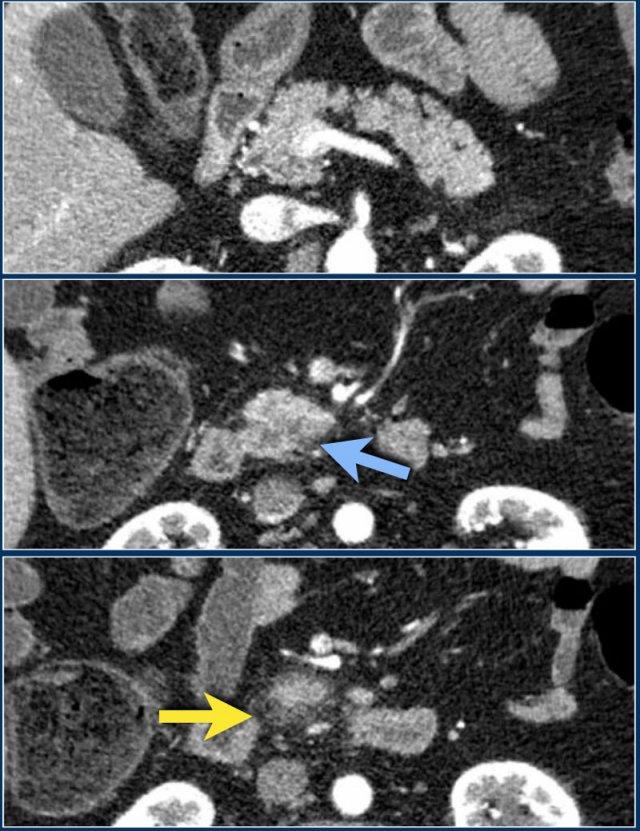

Đây là hình ảnh của một bệnh nhân nhập viện với cơn đau thượng vị cấp tính dữ dội, rất gợi ý viêm tụy cấp.

Tuy nhiên, nồng độ amylase vẫn trong giới hạn bình thường.

CECT đã được thực hiện.

Các kết quả ghi nhận:

- Phần lớn tụy có hình ảnh bình thường.

- Phù nề mỏm móc của đầu tụy (mũi tên xanh lam).

- Phù nề tổ chức mỡ quanh tụy (mũi tên vàng), phù hợp với viêm tụy thể kẽ.

Không có biến chứng và chẩn đoán viêm tụy mức độ nhẹ được xác lập.